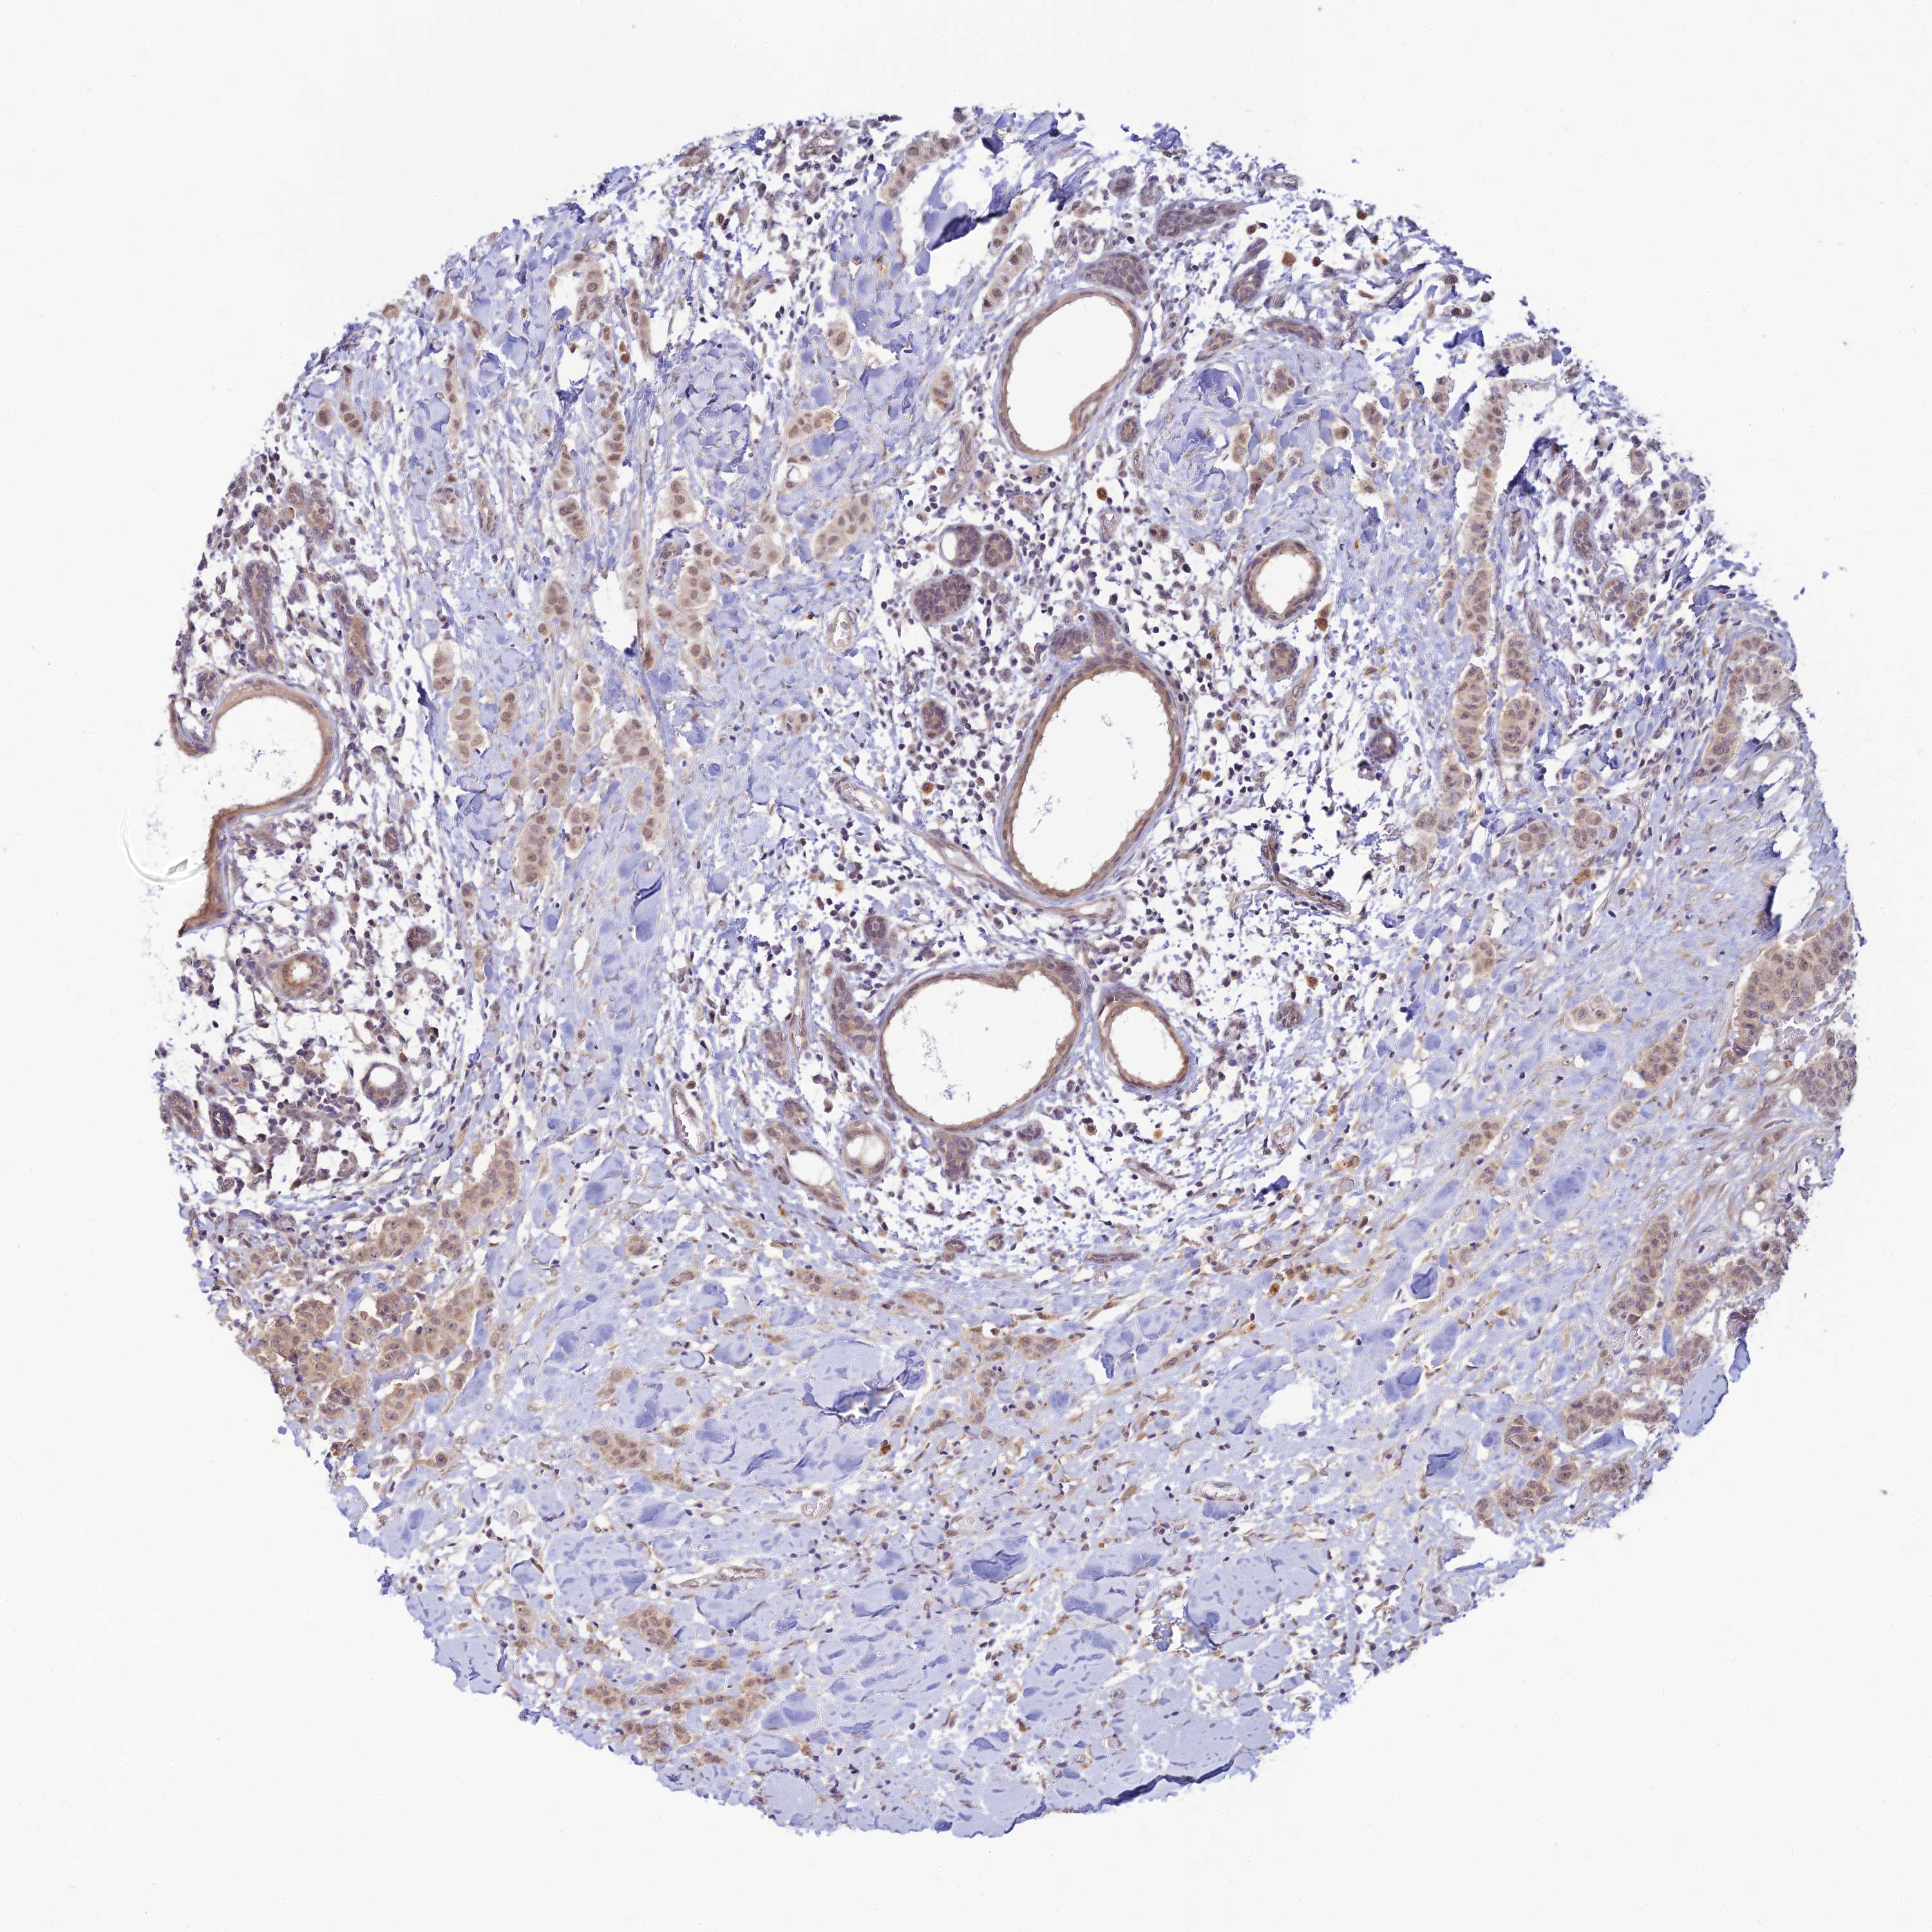

CANCER BREAST CANCER Show tissue menu

BRCA TCGA BRCA VALIDATION PROTEIN EXPRESSION